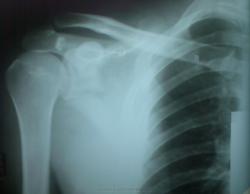

Пол пациента: Мужской пол Тип патологии: Травма Область исследования: Скелетно-мышечная система Методы исследования: Rg Мужчина средних лет. ДТП. Ваше мнение? https://radiomed.ru/sites/default/files/styles/case_slider_image/public/user/2667/Foto008b.jpg?itok=z2RXihxf https://radiomed.ru/sites/default/files/styles/case_slider_image/public/user/2667/Foto009b.jpg?itok=2lHbq_s9 ID:4264 Sun, 30/05/2010 - 17:26 #1 lupan Offline Last seen: 6 years 10 months ago Joined: 07.01.2010 - 17:17 Posts: 1406 1. Подвывих в АКС Iст. 2. Оскольчатый перелом лопатки с/с. 3. Перелом III-IV ребер с/с. 4. Перелом попер. отростков ThI (ThII?) 5. Перелом левого полулунного отростка СVI. 6. Перелом грудинного конца ключицы. 7. Что там с СIII? Ничего не пропустил? Великое преймущество врача заключается в том, что он не обязан следовать собственным советам. ( А. Кристи) Sun, 30/05/2010 - 21:12 #2 stovbav Offline Last seen: 2 years 2 months ago Joined: 20.12.2009 - 17:28 Posts: 7066 Это вряд ли... 6. Перелом грудинного конца ключицы. 7. Что там с СIII? ....все остальное в точку.... Жаль, что не получилось доснять нормально череп, но там еще полетел и суставной отросток нижней челюсти слева... Это я к тому, что сила удара одновременно была направлена справа сзади-вперед, а слева - спереди-назад... Болезни ног: виды, симптомы, причины, профилактика и лечение

1. Подвывих в АКС Iст.

2. Оскольчатый перелом лопатки с/с.

3. Перелом III-IV ребер с/с.

4. Перелом попер. отростков ThI (ThII?)

5. Перелом левого полулунного отростка СVI.

6. Перелом грудинного конца ключицы.

Жаль, что не получилось доснять нормально череп, но там еще полетел и суставной отросток нижней челюсти слева...

Это я к тому, что сила удара одновременно была направлена справа сзади-вперед, а слева - спереди-назад...